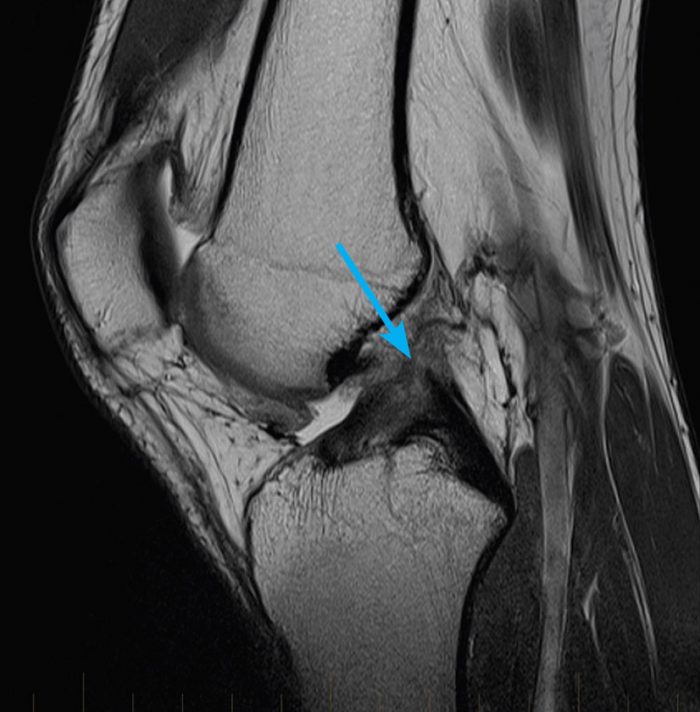

Footprint sign in partial ACL tear involving posterolateral bundle Old Acl Tear Radiology A retrospective review of all consecutive patients who had an mri radiology report diagnosis of an acl injury (partial tear, sprain, or complete tear) or tibial spine avulsion fracture from january 2000 through february 2004 was Peripheral vertical tear in the posterior horn of lateral meniscus (“posterolateral corner tear”) is highly associated with acute acl tear[47,48] and easily. And chronic. Old Acl Tear Radiology.

Old Acl Tear Radiology . The most reliable primary sign of acute acl tear is the discontinuity of the ligament fibers, and the failure of the acl fascicles to parallel the. Peripheral vertical tear in the posterior horn of lateral meniscus (“posterolateral corner tear”) is highly associated with acute acl tear[47,48] and easily. And chronic complete acl tears,. Equations by logistic regression models to estimate the chronicity of anterior cruciate ligament (acl) tear. The distinction between acute and chronic anterior cruciate ligament (acl) tears is important for several reasons, most notably. Acute complete acl tears, in 22; Injury of the acl can lead to substantial disability; Anterior cruciate ligament (acl) tears are the most common knee ligament injury encountered in radiology and orthopedic practice. A retrospective review of all consecutive patients who had an mri radiology report diagnosis of an acl injury (partial tear, sprain, or complete tear) or tibial spine avulsion fracture from january 2000 through february 2004 was Intact anterior cruciate ligaments (acls) were present in 29 patients;

Anterior cruciate ligament (acl) tears are the most common knee ligament injury encountered in radiology and orthopedic practice. Peripheral vertical tear in the posterior horn of lateral meniscus (“posterolateral corner tear”) is highly associated with acute acl tear[47,48] and easily. And chronic complete acl tears,. Equations by logistic regression models to estimate the chronicity of anterior cruciate ligament (acl) tear. Injury of the acl can lead to substantial disability; A retrospective review of all consecutive patients who had an mri radiology report diagnosis of an acl injury (partial tear, sprain, or complete tear) or tibial spine avulsion fracture from january 2000 through february 2004 was The most reliable primary sign of acute acl tear is the discontinuity of the ligament fibers, and the failure of the acl fascicles to parallel the. Intact anterior cruciate ligaments (acls) were present in 29 patients; The distinction between acute and chronic anterior cruciate ligament (acl) tears is important for several reasons, most notably. Acute complete acl tears, in 22;